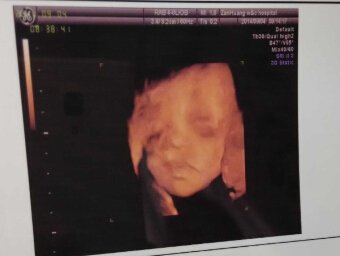

14年9月5日 怀孕27周 在县妇幼保健院 做四维彩超 大夫说没事 我看了单子 感觉嘴巴左上方一 片模糊。怕是唇腭裂。因为我老公就是唇腭裂。希望医生帮忙看看四维彩超的单子。看看有没有问题。是否需要再做一个四维彩超确认一下?我超级担心,因为我老公就是唇腭裂。求大夫。给一个参考。 点击展开 匿名用户 2014-09-05 01:12 为您推荐: 其他回答 你好,这个是可以的呢,我觉得你这个是要自己注意去进一步的确认一下的呢,这样是会好点的啊 陈颖医生 2014-09-05 14:26 相关问题 你们好,有临沭县的吗?我现在四个月了,想查查胎儿健康发育怎么样,想在妇幼保健院做四维彩超的,要怎么预约大夫呢,其他的还需要做什么检查吗? 宝妈们都来说说南京市妇幼保健院都有哪些推荐的大夫吧,互相做个参考~~~ 宝妈们都来说说合肥市妇幼保健院都有哪些推荐的大夫吧,互相做个参考~~~